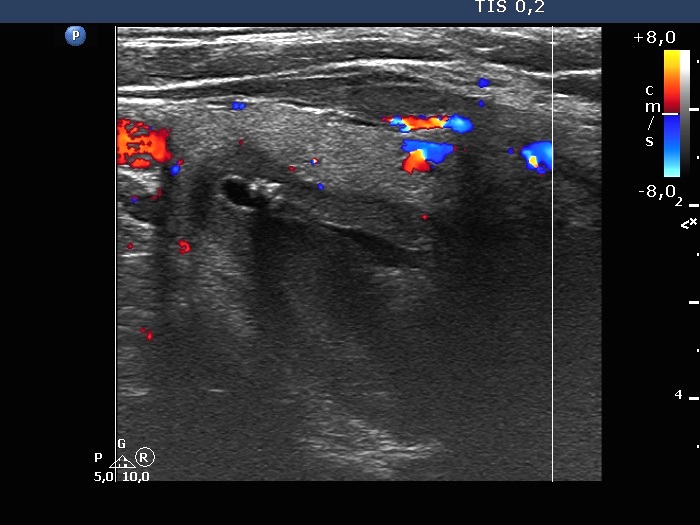

Right lobe, longitudinal scan

Right lobe, transverse scan - after aspirating 16 mL yellow fluid. The central cystic area became much smaller.